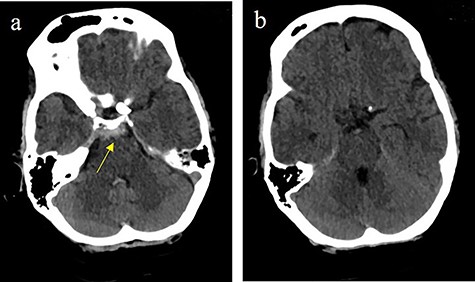

Subarachnoidal bleeding into the basal cistern-axial cranial computed tomography (cCT) at the level of (a) prepontine cistern (arrow) and (b) pentagonal cistern.

On the next day (Day 9 post-op), the patient suffered from acute and devastating headaches, with screaming and enuresis. An emergency computed tomography (CT) was carried out and displayed a prepontine and retroclival subarachnoid hemorrhage (Hunt & Hess Grade I), (Fig. 2). For further evaluation, a digital subtraction angiography (DSA) was conducted, and it showed a pseudoaneurysm of ophthalmic1/supraclinoid2/C23 part of the left ICA, which was directly treated by a flow diverter (Derivo®—4,5/20), with remaining rest flow (Fig. 3). The patient was transferred to the ICU, transcranial doppler sonography was performed and revealed normal flow. In the following course, the patient suffered from Terson’s syndrome and hyponatremia due to SIADH, but after clinical improvement, was transferred back to normal station after 10 days of post-operative monitoring. Furthermore, the patient was plagued with cephalgia and nausea, which could not be compensated with analgetics and antiemetics. On the 20th post-operative day after the epileptic seizure with postictal vigilance reduction, an emergency CTA was conducted showing progressive SAH (Fig. 4) and a growing pseudoaneurysm as well as generalized vasospasm with posthemorrhagic hydrocephalus. For an emergency CSF diversion, an external ventricle drain was placed. The repeated DSA showed a growing false aneurysm which was treated with two additional flow diverters (2× Derivo®—4,5/20) as well as coiling (HydroSoft™ 2/3 and 2× 1,5/2) by endoleak (Fig. 5). The vasospasms were treated by an intraarterial spasmolysis (Fig. 6).